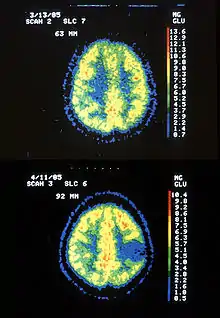

Hypermetabolism is one symptom of Astrocytoma. Shown above is a PET scan of hypermetabolic Astrocytoma in the brain.